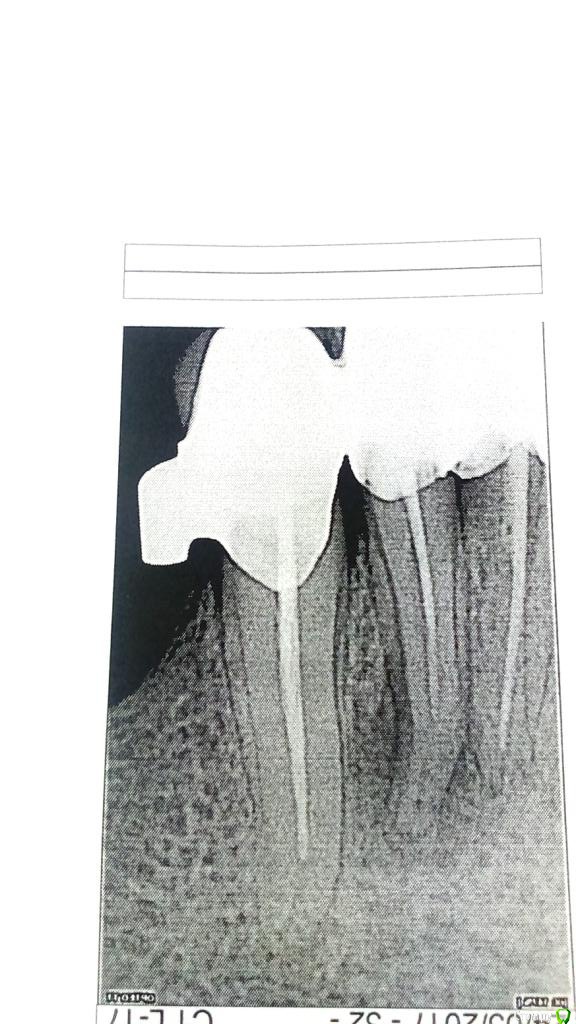

Наина 1973 Опубликовано 24 мая, 2017 Поделиться Опубликовано 24 мая, 2017 Ситуация такова: ничего не болело, образовался свищ, обратилась в клинику - предложили три варианта: удаление зуба, снять коронки и пролечить зуб, сделать ретроградное пломбирование.Снимок на тот момент не дали на руки.Пока я думала и работала врач уехал.Обратилась к другому хирургу, он снимок сделал, сказал что все плохо, все зубы не до пломбированы (лечение в этой же клиники проходила, в карте терапевта есть снимки год назад там было все нормально при установке коронок).Ретроградное пломбирование в этом случае они не делают и в данном случае только резекция верхушки, положить лекарство (не помню как назвали) и жить и надеяться на то что больше они может не воспаляться.Обошла четыре клиники в нашем городе, все говорят про резекцию, в двух вообще сказали, что только снятие коронок.Выехать в другой город для лечения не вариант, я живу в Магадане проезд туда-обратно (без разницы Москва или Хабаровск) сейчас порядка 40-50 тыс.Снять коронки пока не могу, так как там бюгель и сделать конструкцию новую очень дорогоСнимок прикрепляю, он на бумаге, поэтому фотала под разным освещением на всякий случай.Вопрос:- делать или нет резекцию или ходить так дальше и ждать отпуска что бы обратиться в стоматологию в другом городе?- если будет только резекция, вероятность рецидива очень большая? и в случае рецидива только удаление зуба?Спасибо Ссылка на комментарий

Fibez Опубликовано 24 мая, 2017 Поделиться Опубликовано 24 мая, 2017 1. резекцию без ретроградного пломбирования не делать2. если снимать коронки не хочется (+там замковый бюгель? это повлечет за собой и его переделку), то искать терапевта, который возьмется сделать эндо через коронку.3.вероятность рецидива большая4.не обязательно, просто при обострении у Вас будет меньше времени выбирать Ссылка на комментарий

DmitrySH Опубликовано 24 мая, 2017 Поделиться Опубликовано 24 мая, 2017 Через коронку ничего сложного, но нижние резцы имеют такое стоение, что от коронки мало что останется. Вся керамика поколется скорее всего. 3 Ссылка на комментарий